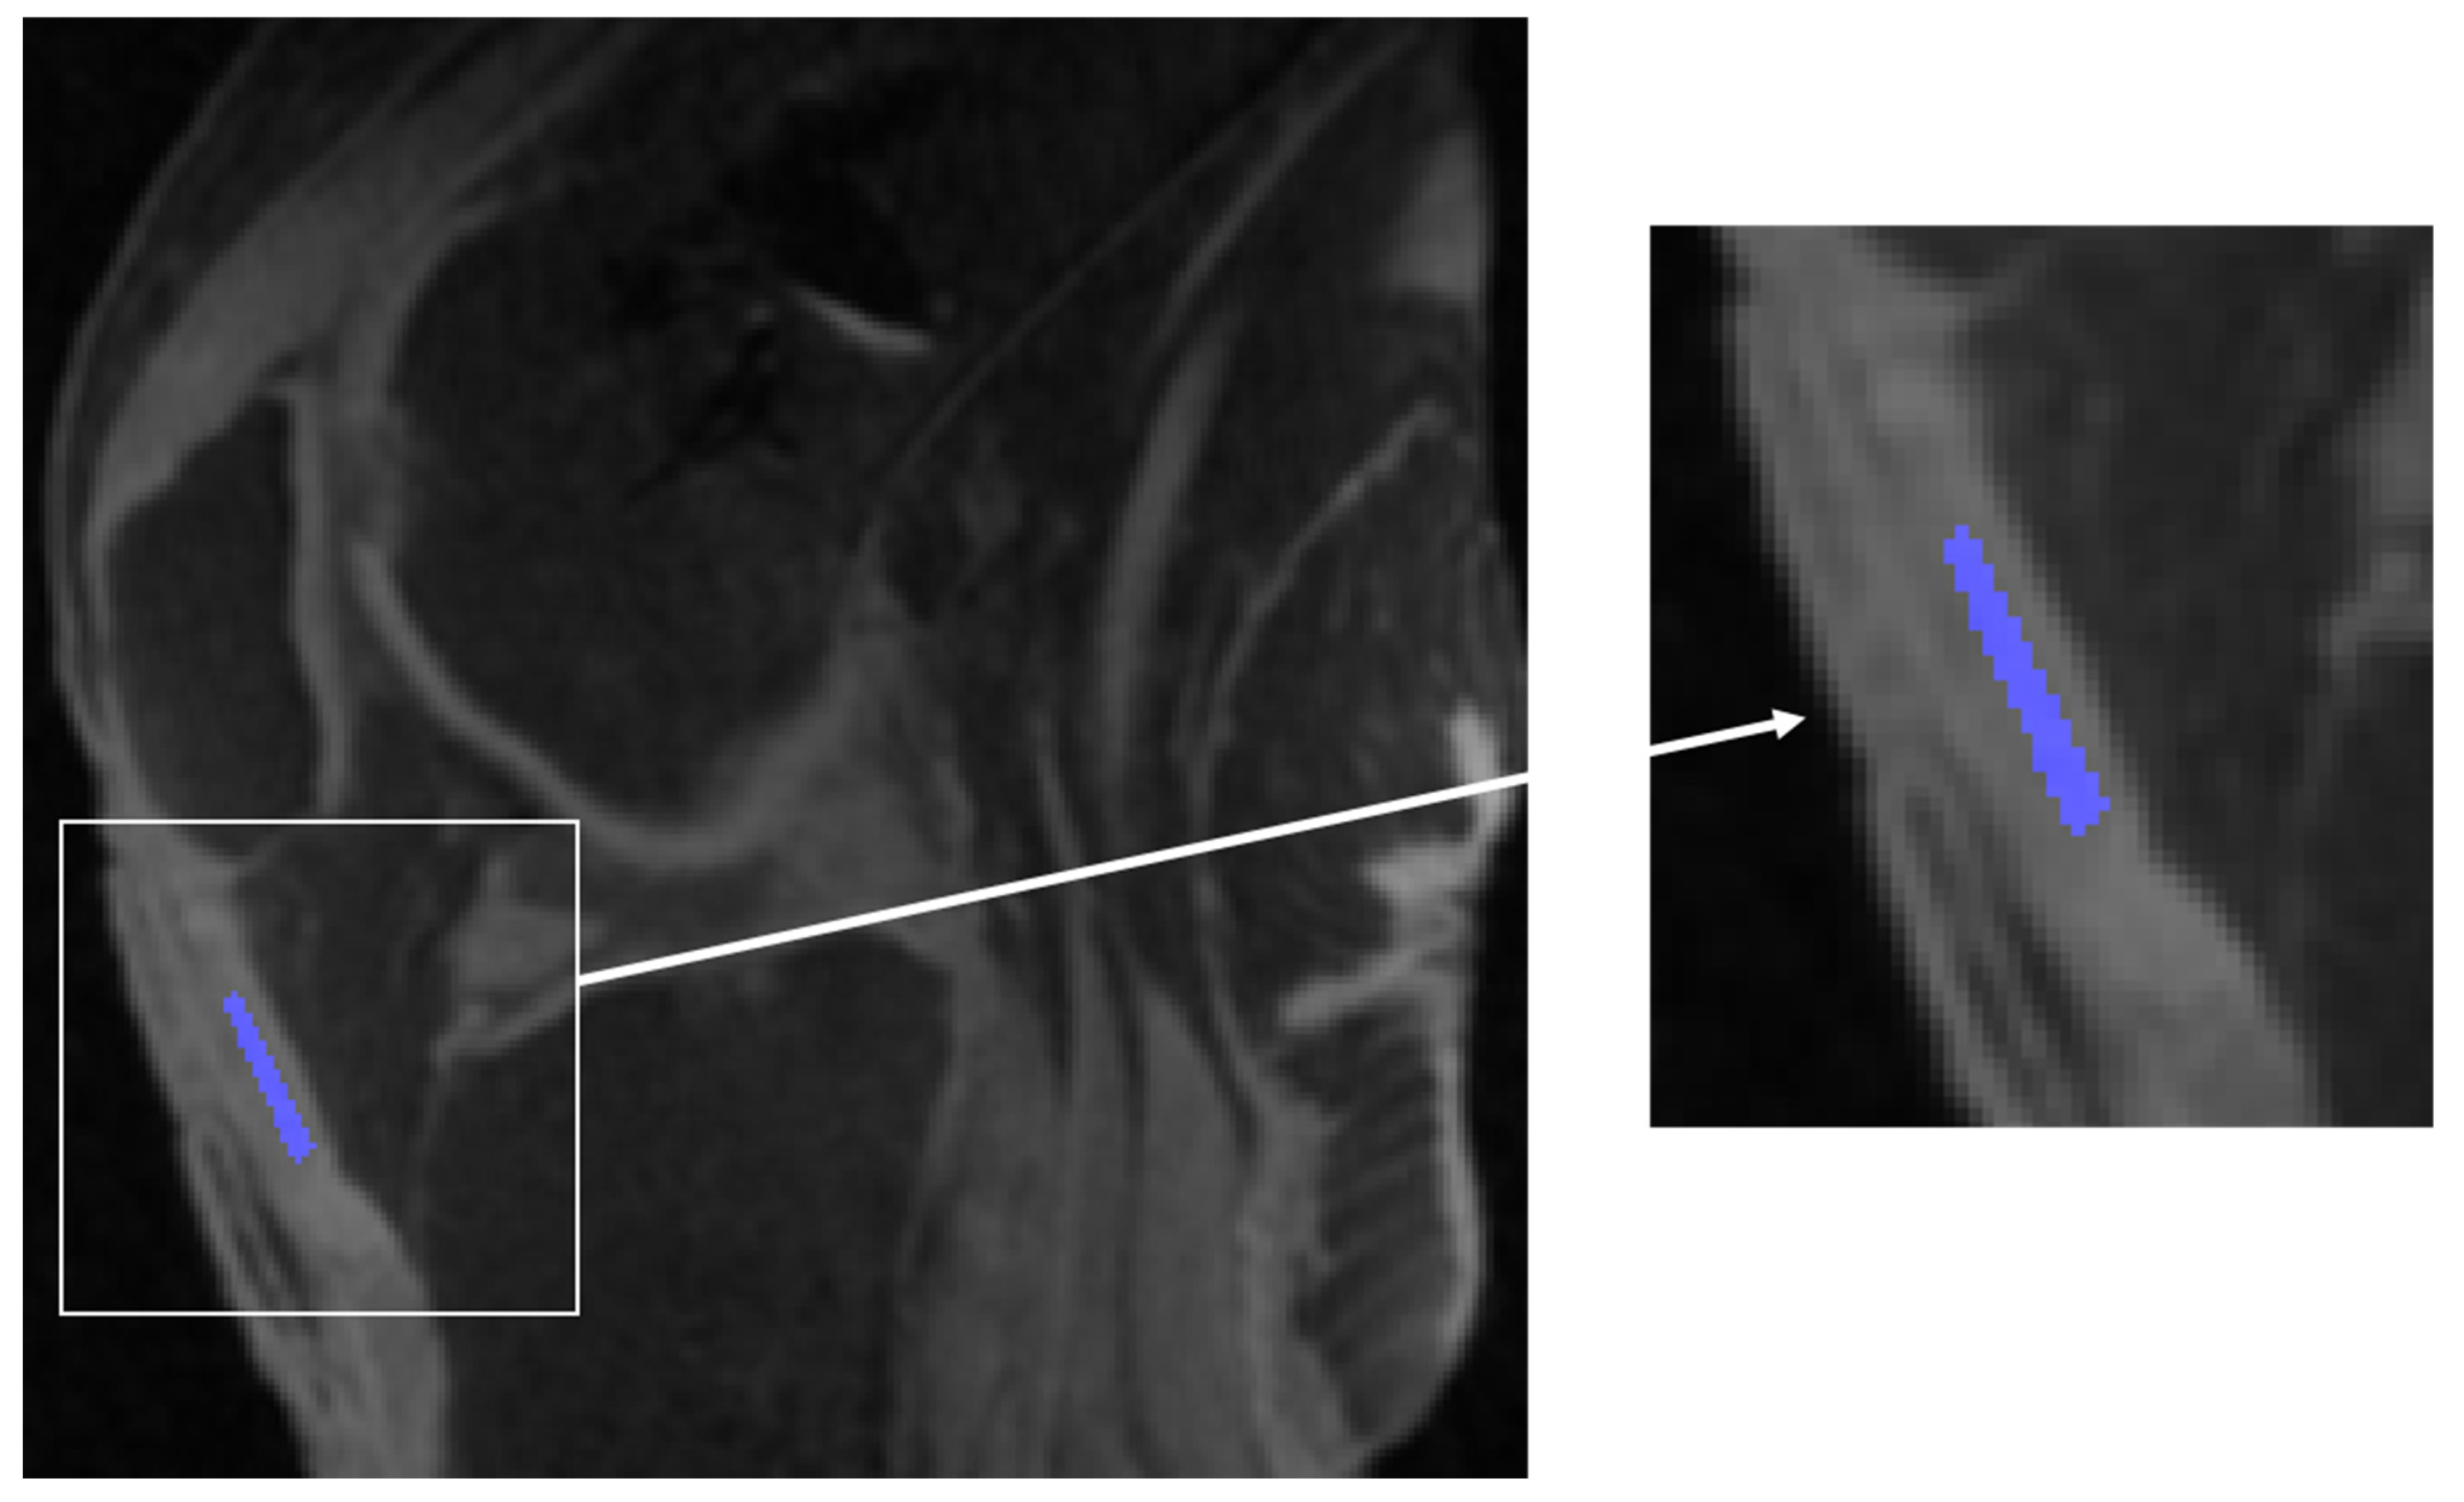

Malhi, B.S.; Moazamian, D.; Shin, S.H.; Athertya, J.S.; Silva, L.; Jerban, S.; Jang, H.; Chang, E.; Ma, Y.; Carl, M.; et al. Bi-Exponential 3D UTE-T1ρ Relaxation Mapping of Ex Vivo Human Knee Patellar Tendon at 3T. Bioengineering 2024, 11, 66. https://doi.org/10.3390/bioengineering11010066